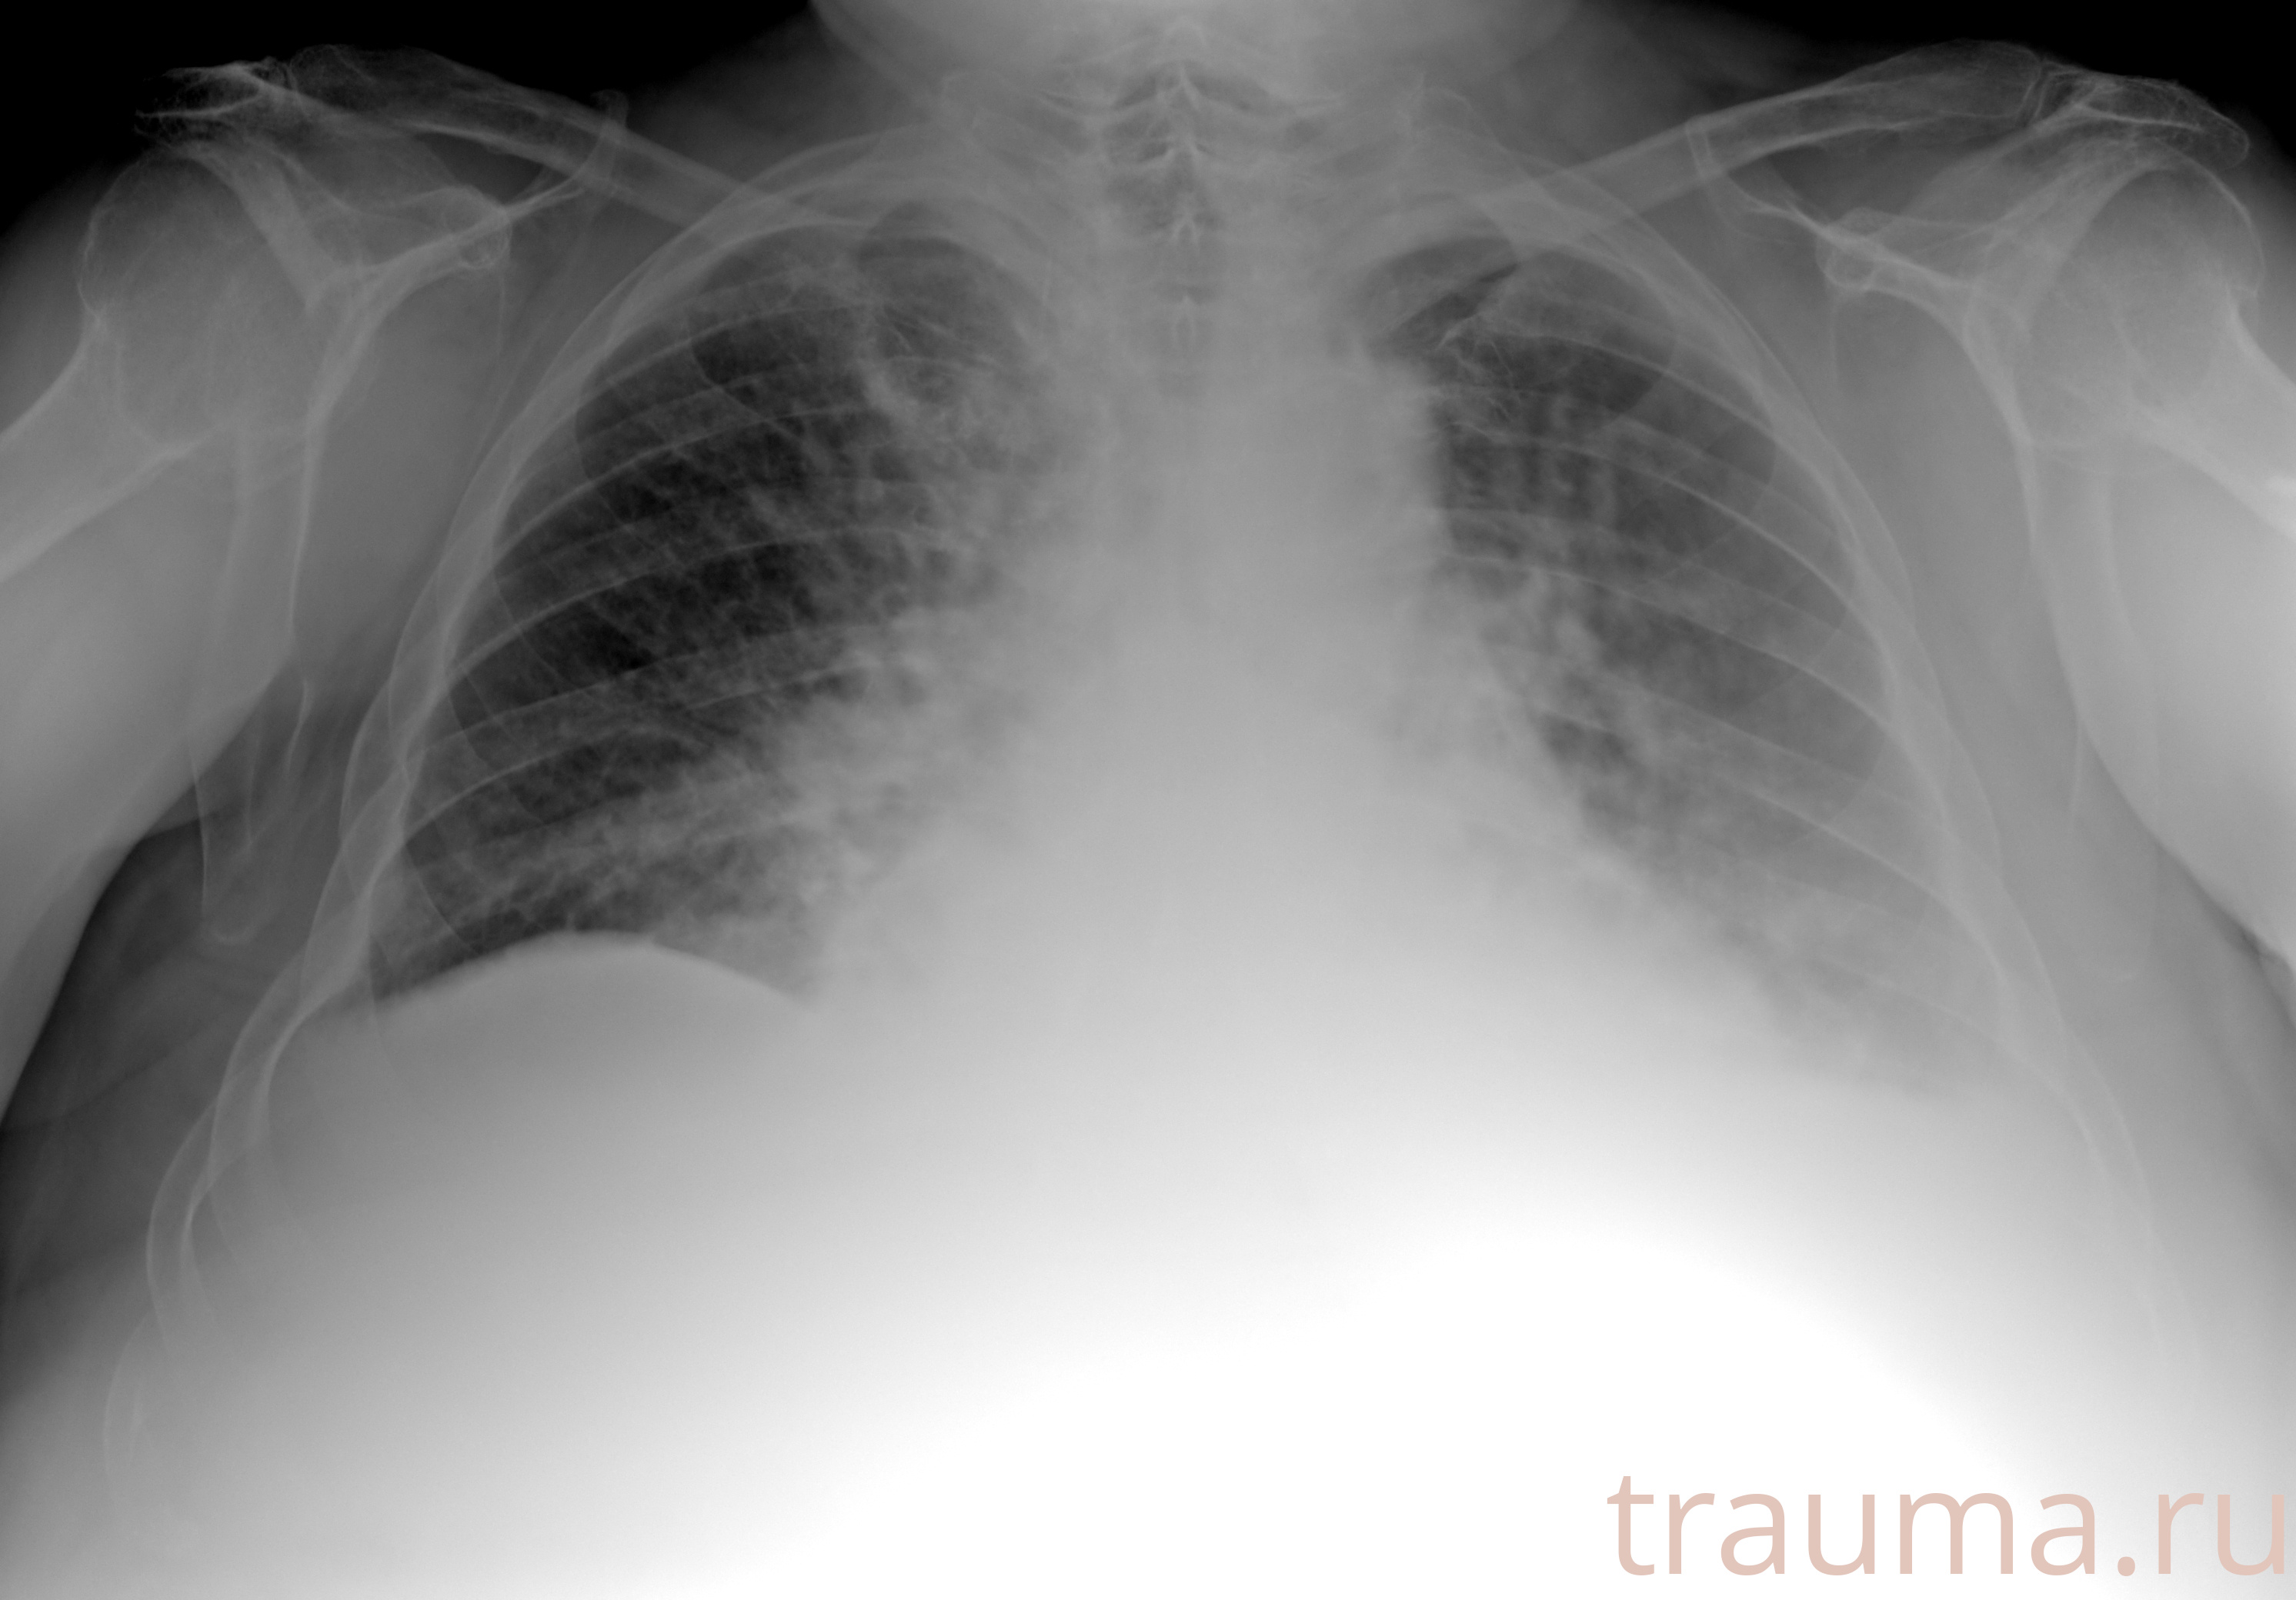

Рентген на дому: по вашему адресу приезжает врач-рентгенолог, травматолог-ортопед с мобильным рентгеновским аппаратом, проводит диагностику травмы или заболевания, делает необходимые рентгенограммы, дает рекомендации по дальнейшему лечению. Получить качественные снимки в домашних условиях возможно благодаря уникальной методике, разработанной МосРентген Центром для института  Склифосовского